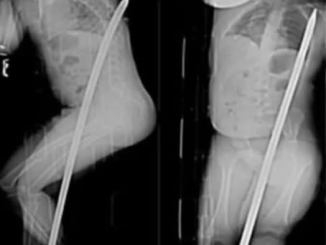

El “embarazo” que desconcertó a los médicos: ¿Qué crecía realmente dentro de esta mujer de 50 años?

La olla cayó al suelo de la cocina con un estrépito, salpicando la comida sobre las baldosas limpias. Rosa jadeó, llevándose la mano al estómago […]